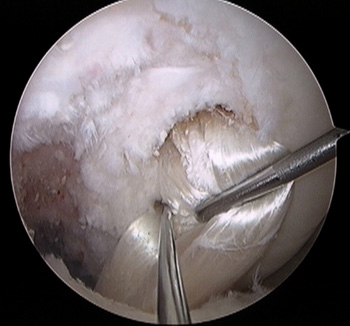

maestu1_fig7

Figura 7: vista artroscópica desde portal anterolateral de fijación femoral en simple banda en una rodilla izquierda.